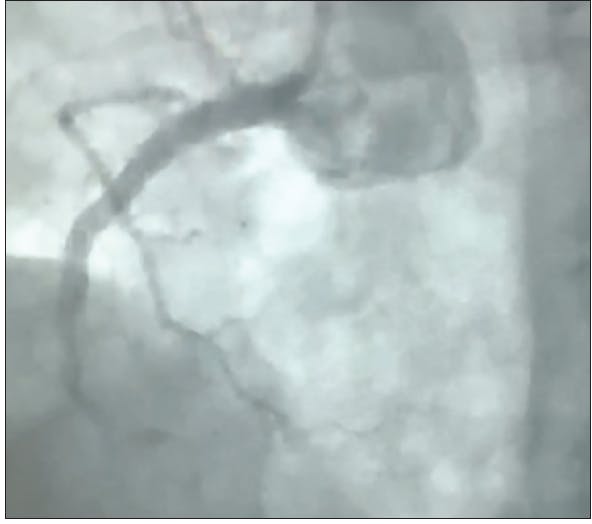

Prior to the procedure, ticagrelor was administered and the patient was taken to the cardiac cath lab for angiography. The initial angiogram revealed TIMI 0 flow in the proximal right coronary artery (RCA) due to plaque rupture. The patient received a 3.5- X 38-mm everolimus-eluting stent (Synergy™ drug-eluting stent [DES], Boston Scientific Corporation) with postdilation optimized by intravascular ultrasound (IVUS) and was then sent to the step-down unit. The patient vomited the ticagrelor within 2 hours of administration and cangrelor was started. Due to continual vomiting, an electrocardiogram was obtained that showed an acute MI. The patient was brought back to the cardiac cath lab for follow-up angiography that revealed TIMI 0 flow of the RCA (Figure 1).

INTERVENTION

Manual aspiration using a Pronto V3 (Teleflex) catheter restored some flow, however, distal embolization to the posterior descending artery (PDA) immediately caused right ventricular cardiac arrest (Figure 2). The patient underwent six shocks and was intubated while CAT RX was delivered through the freshly placed 3.5- X 38-mm DES to the PDA. Two passes of CAT RX with the Penumbra ENGINE resulted in TIMI 3 flow restoration and retrieval of the distal emboli from the PDA (Figure 3). The patient’s symptoms normalized, the electrocardiogram stabilized, and the acute MI was immediately resolved. The patient remained on cangrelor with no need for tirofiban.